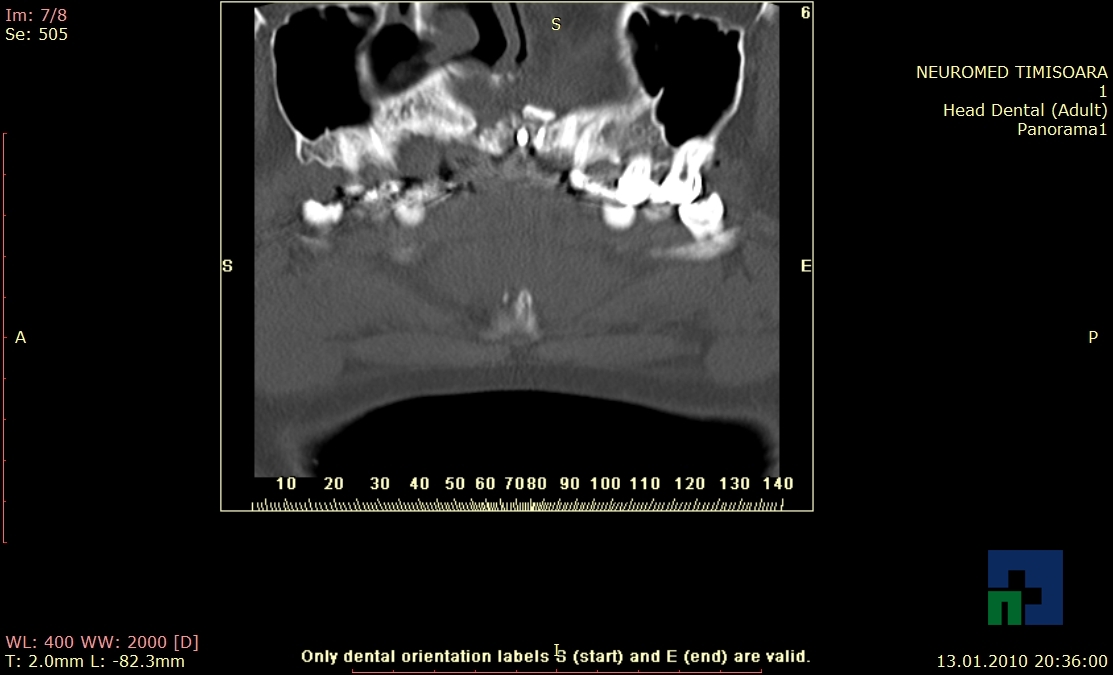

- Diagnosticul fracturilor:

- Complexe cranio-sinusale

- Complexe cranio-etmoidale

- Complexe cranio-orbitare

- Complexe cranio-faciale